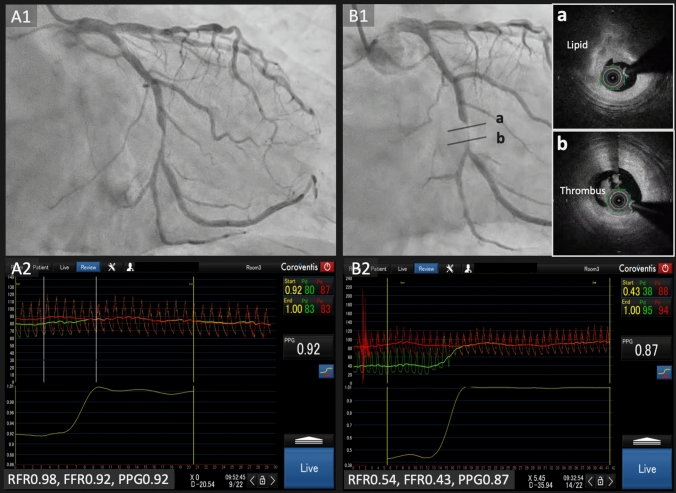

Unmasking the hidden risk: potential implication of pullback pressure gradient in ischemia-negative lesions.

{"title":"Unmasking the hidden risk: potential implication of pullback pressure gradient in ischemia-negative lesions.","authors":"Hirohiko Ando, Carlos Collet, Koshiro Sakai, Hirofumi Ohashi, Tetsuya Amano","doi":"10.1007/s12928-025-01147-0","DOIUrl":null,"url":null,"abstract":"","PeriodicalId":9439,"journal":{"name":"Cardiovascular Intervention and Therapeutics","volume":" ","pages":"1007-1008"},"PeriodicalIF":5.8000,"publicationDate":"2025-10-01","publicationTypes":"Journal Article","fieldsOfStudy":null,"isOpenAccess":false,"openAccessPdf":"https://www.ncbi.nlm.nih.gov/pmc/articles/PMC12476381/pdf/","citationCount":"0","resultStr":null,"platform":"Semanticscholar","paperid":null,"PeriodicalName":"Cardiovascular Intervention and Therapeutics","FirstCategoryId":"1085","ListUrlMain":"https://doi.org/10.1007/s12928-025-01147-0","RegionNum":0,"RegionCategory":null,"ArticlePicture":[],"TitleCN":null,"AbstractTextCN":null,"PMCID":null,"EPubDate":"2025/7/2 0:00:00","PubModel":"Epub","JCR":"Q2","JCRName":"CARDIAC & CARDIOVASCULAR SYSTEMS","Score":null,"Total":0}